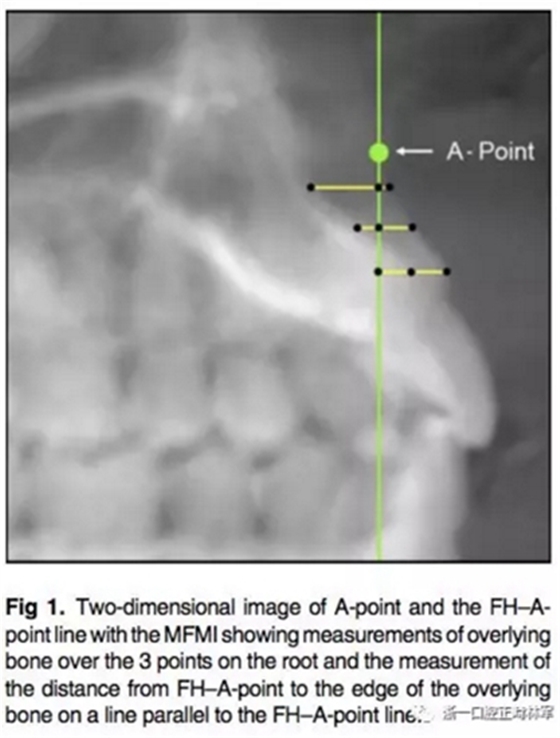

所有圖像導(dǎo)入Dolphin軟件中進(jìn)行處理,2D側(cè)位圖像為使用Dolphin軟件使用相同的標(biāo)準(zhǔn)切割CBCT獲得。使用眶耳平面(FH)作為水平參考平面,使用垂直于眶耳平面(FH)同時(shí)通過(guò)A點(diǎn)的直線作為垂直參考平面。在上切牙最前點(diǎn)進(jìn)行定點(diǎn),牙根分界為自釉牙骨質(zhì)界至根尖,在牙根根尖、牙長(zhǎng)1/2處、釉牙骨質(zhì)界下3mm處進(jìn)行定點(diǎn)。使用FH的平行線測(cè)量頰側(cè)牙槽骨至牙根上3點(diǎn)的距離,同時(shí)測(cè)量A點(diǎn)與以上三條線段的距離,如圖所示。測(cè)量切牙的轉(zhuǎn)矩,使用通過(guò)切點(diǎn)、根尖的直線與FH平面的所成角。

在CBCT的3D圖像上使用右側(cè)耳點(diǎn)與眶下點(diǎn)定FH平面。同樣定好過(guò)A點(diǎn)與FH垂直的垂直參考線,測(cè)量牙根上點(diǎn)至垂直參考線的距離。

根據(jù)每顆切牙相對(duì)上頜骨的位置在同一平行切面上各自確定A點(diǎn),定好切牙最前點(diǎn)(MFMI),牙根長(zhǎng)度依然為釉牙骨質(zhì)界至根尖點(diǎn)。使用與2D側(cè)位片上相同的方法進(jìn)行牙根至骨皮質(zhì)的測(cè)量。轉(zhuǎn)矩的測(cè)量也同2D側(cè)位片。